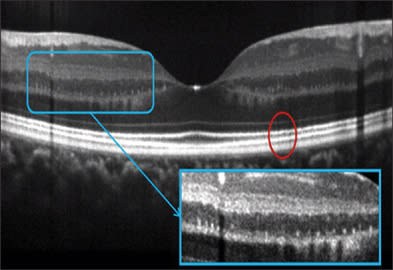

Figure 6. Frame-averaged OCT image provide details of the outer retinal layers in this case of drusenoid pigment epithelial detachment (PED). Photoreceptor atrophy reduces the distance between the outer plexiform layer to the pigment epithelium from 122-150 microns to 59 micron over the PED, with loss of the bright lines at the external limiting membrane and photoreceptor inner-outer segment junction. Bruch's membrane could be visualized at the base of the PED. Frame averaging also boost the signal and helps one visualize the choroid-sclera junction. The Optovue RTVue FD-OCT system was used.